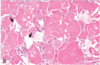

Pathological process that accounts for this appearance?

Degeneration / Necrosis